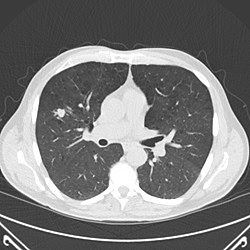

• Lung Cancer Screening : CT Scan

Lung Cancer Screening : CT Scan

Those recommended for yearly lung cancer are aged 55 to 74 years and in fairly good health, currently smoke or have quit smoking in the past 15 years, and have at least a 30 pack-year smoking history. Screening is done with a low-dose CT scan.